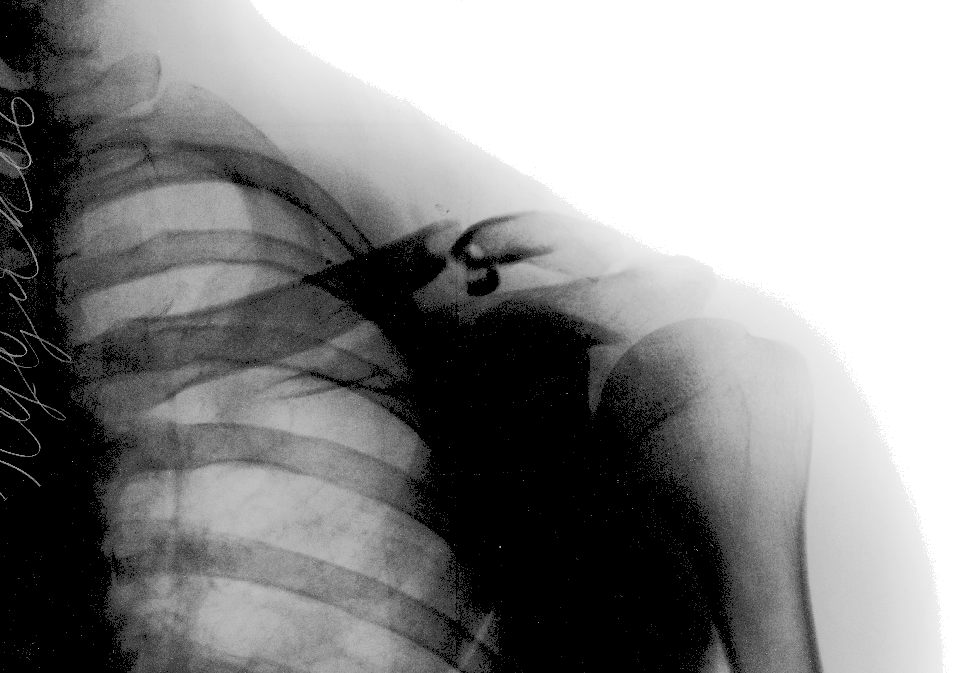

У меня было так:

Вправили в травмпункте Склифа, стало вот так: